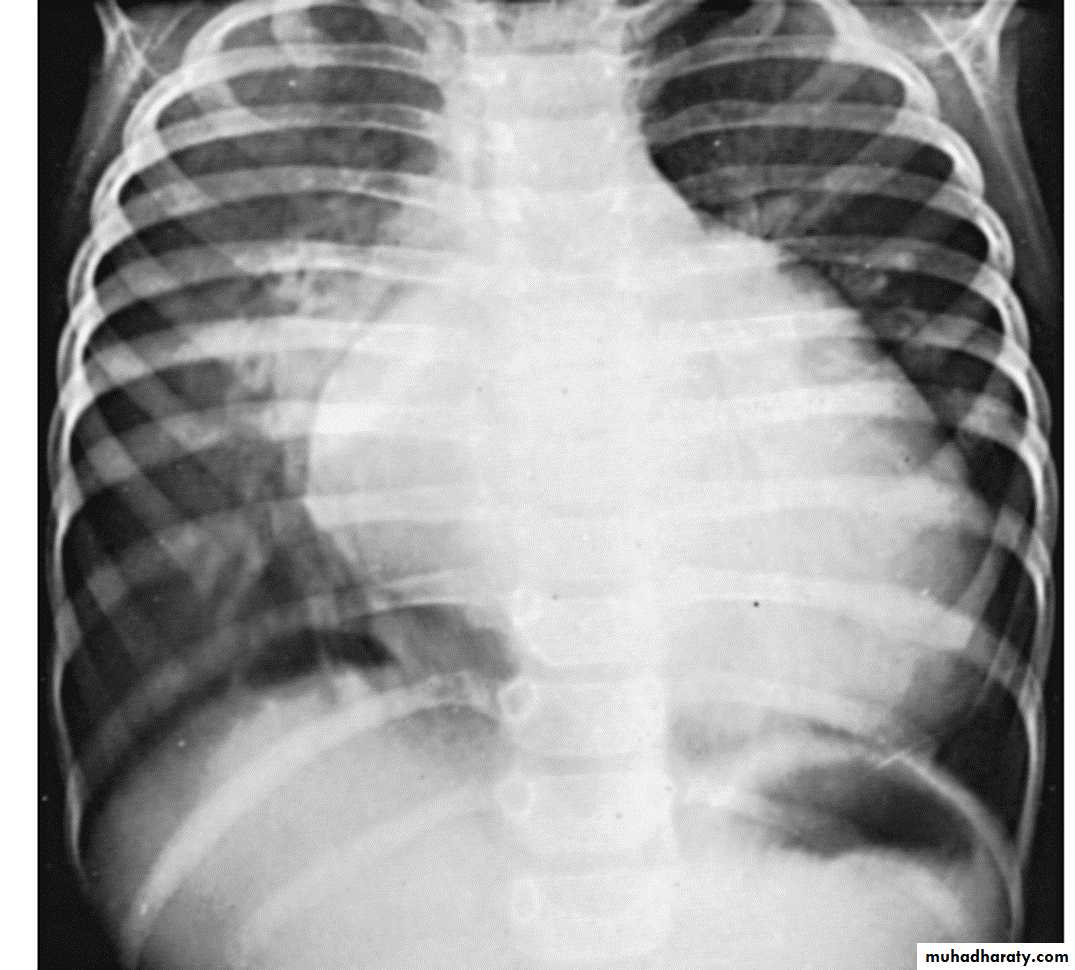

1- Chest-X ray show cardiac enlargement. Pulmonary vascularity is variable and depends on the cause of the heart failure. The cardiothoracic ratio (C/T ratio) is higher than the normal for age.Normal C/T ratios

Infants < 55 %

Older children < 50%